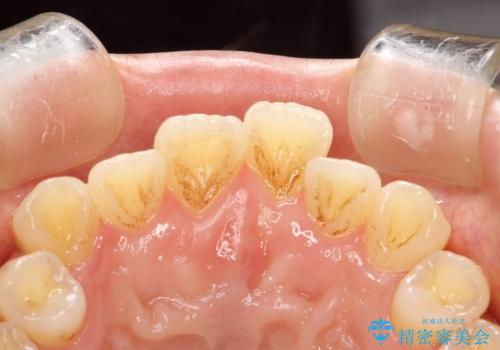

- 全体の歯にうっすらと茶渋によるステインが見られます。

よく見ると歯自体はあまり黄色くないので、ステインによって歯が黄色く見えてしまっています。

PMTCというクリーニングを行うことでステインは除去できるので、今回はPMTC(エアフロー)の60分コースにて全体のクリーニングを行いました。

エアフローは歯と歯の間や、詰め物との境目などブラシやチップが届かないところまで細かくお掃除が可能になります。